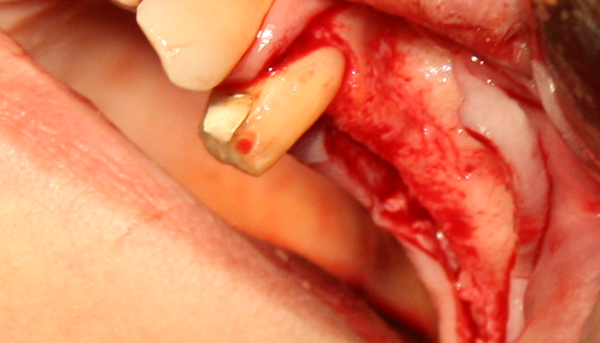

Отворен максиларен синус в началото на интервенцията. Случаят е интересен със следното - твърде атипична форма на трепанационния отвор. На какво се дължи на това - на лошо планиране на оперативния достъп или на нещо друго? Дължи се на факта, че отначало въпросната намеса беше планирана като балонен синуслифт; за съжаление обаче мембраната на синуса се разкъса и надуването на балона стана невъзможно.